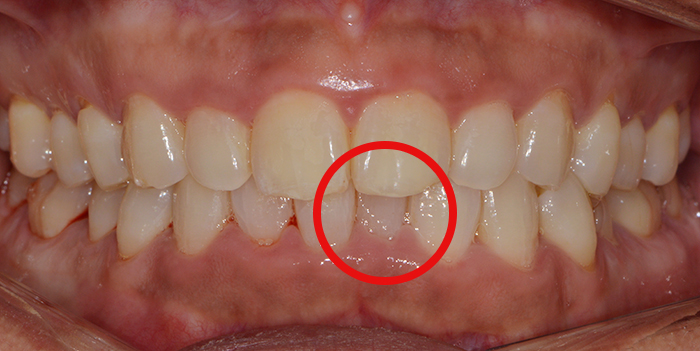

우선 환자분 사진을 한번 살펴보도록 할께요. 사진상 빨간색으로 표시한 부분이 다른 치아 보다 안쪽으로 들어가 있는 게 보이시죠?

전체적인 치열을 확인하기 위해서는 정면에서 찍은것보다 아래와 같이 입을 벌린 상태에서 찍은 모습을 보면 보다 자세히 알 수 있습니다.

앞에서 말씀드린 것처럼 빨간색으로 표시한 부분의 한쪽이 안쪽으로 삐뚤게 꺾여있네요. 그리고 주변 치아들도 몇개도 고르지 않고 올 바른 치열을 방해하고 있는 것이 보이시죠?